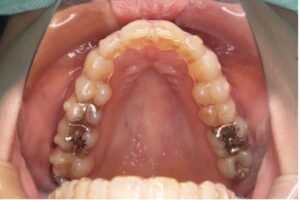

上下ともブラケットを裏側につける、もっとも見えないワイヤー矯正です。

正面からはほぼ見えないため審美性を重視したい方にはメリットが大きい矯正方法ですが、これまでの矯正装置の中で一番舌に当たりやすいため、発音がしづらく慣れるまでは強い違和感があります。また、料金も一番高価です。